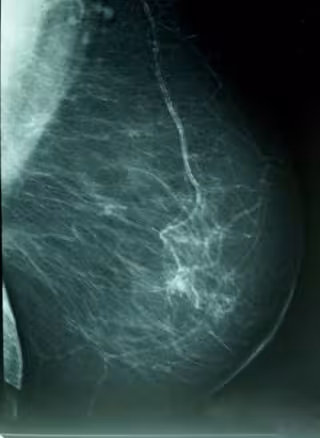

Cáncer De Mama, Densidad Mamográfica

Foto: WIKIPEDIA/A. AVENDAÑO